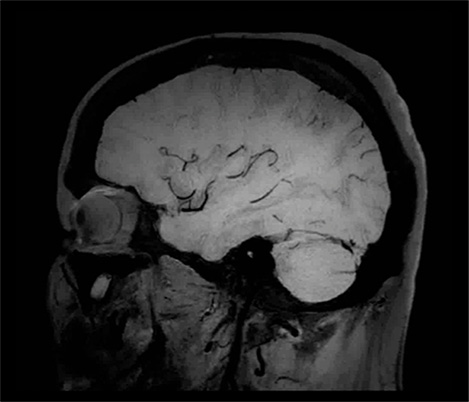

Da colaboração O Dr. Tetsuya Yoneda, Universidade de Kumamoto, Japão, fala sobre a sua colaboração com a Philips numa técnica denominada SWIp desenvolvida para a imagiologia com suscetibilidade ponderada.

...à prática clínica O Dr. Chip Truwit, Hennepin County Medical Center, Minneapolis, EUA, explica como o SWIp se tornou parte integrante de todos as exames de lesões de RM.